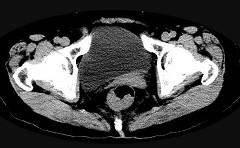

问题 男,56岁,排便形状改变,便不尽感,CT检查如图所示,下列说法正确的是()

选项 A.肠壁上有蒂状新生物 B.其表面光滑,边界清楚 C.肠腔未见狭窄 D.此为直肠息肉 E.此为直肠癌

答案 E